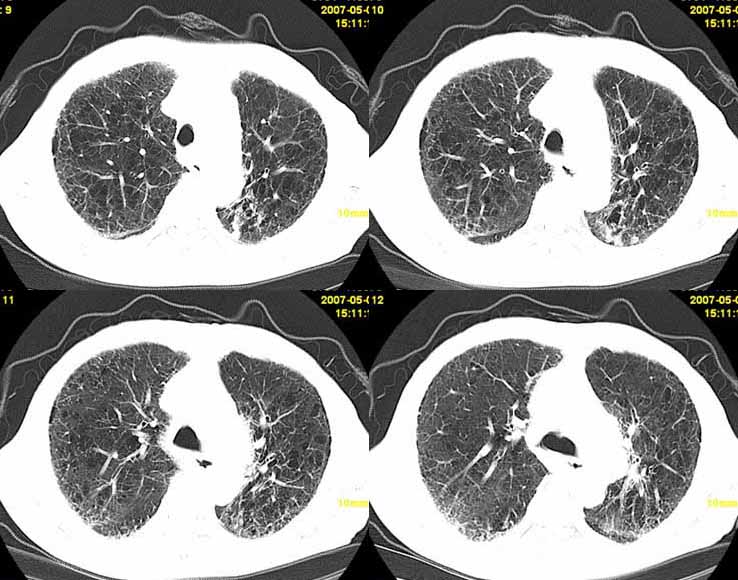

以下是引用小初学者在2007-5-12 11:09:00的发言:[br][br]双肺弥漫性质纤维化(考虑矽肺所致),并发左肺下叶背段周围性肺癌纵隔淋巴转移。

以下是引用zhangzhongshou在2007-5-12 12:09:00的发言:[br]1、左下叶背段周围型肺癌左肺门及纵隔淋巴结转移可能性大。[br]2、弥漫性肺气肿(双侧)。[br]3、双肺间质纤维化。

以下是引用老爱克斯新网客在2007-5-12 12:54:00的发言:[br]1周围型肺癌纵隔肺门淋巴结转移,2肺间质纤维化,